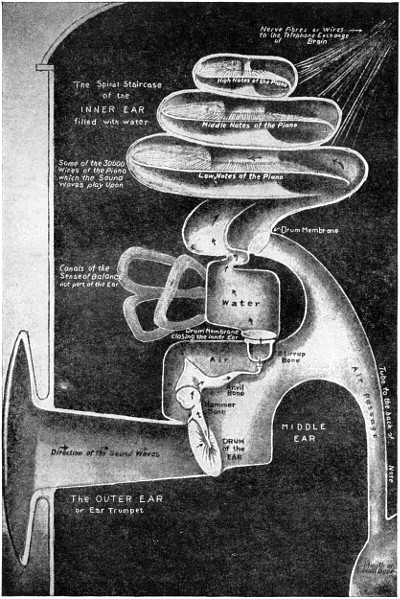

Picture Diagrams of Eye and Ear

ITS STRUCTURE—ORGANIZATION INTO SYSTEMS—FUNCTIONS—SPECIAL SENSES—NERVOUS SYSTEM—PERSONAL HYGIENE—PREVENTION OF DISEASE—INTERDEPENDENCE OF BODY AND MIND—EUGENICS—ILLUSTRATIONS AND CHARTS.